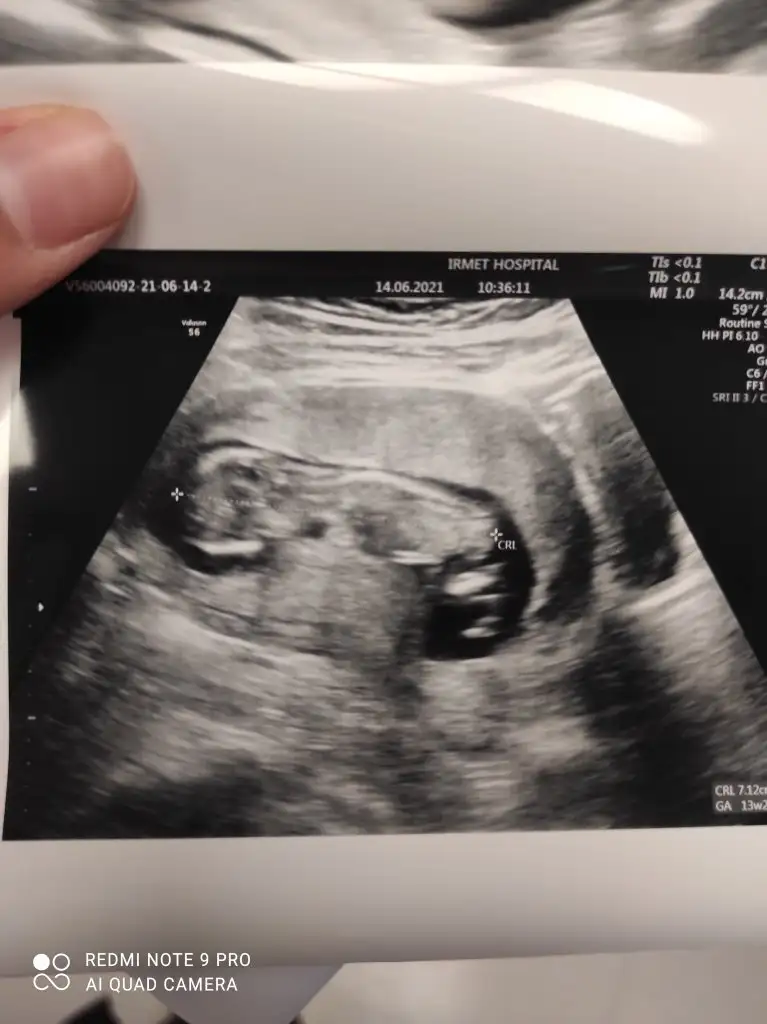

Merhaba erkek demiştin doktor bugün tahmin yaptı erkege benziyor dedi ☺️iki hafta sonra net söyler herhalde değişmezse doğru bildiniz buda 12+3 görüntülerimiz